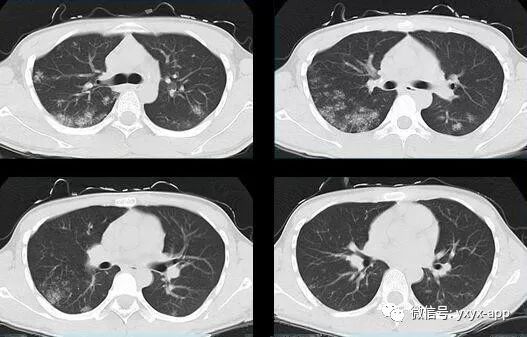

评论:两肺斑片状磨玻璃影,与周围组织分界清楚,呈“地图样”表现,部分病变延伸至胸膜下,部分小叶间隔增厚,气管居中,肺门及纵膈未见肿大淋巴结影,未见胸腔积液。患者青年男性,临床症状轻微影像表现严重,抗炎治疗无效。考虑肺泡蛋白沉积症

1、两肺较淡的斑片状磨玻璃影,不呈叶段分布,病变可延伸至胸膜下,其中磨玻璃影中可见小结节影,磨玻璃影与正常肺组织分界清楚,形成“地图样”改变,这种地图样分布的原因,可能是由于这种斑片影以肺小叶为病变单位,小叶间隔在一定程度上限制了病变的蔓延;

2、由于小叶间隔和小叶内间隔的增厚形成网格状阴影改变,弥漫的磨玻璃影及其内部的网格小叶间隔增厚形成了“铺路石样”改变;

3、实变区具有多样性,多种不同程度的病变共存,病灶内可见支气管气像;

4、病变部位以肺门及双下肺明显。